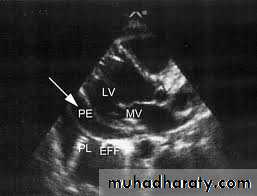

-Ultrasonography is more accurate than plain chest radiography for determining the volume of pleural fluid and frequently provides additional helpful information.

Visualization of fluid facilitates skin marking to indicate a site for safe needle aspiration and guides pleural biopsy, increasing diagnostic yield